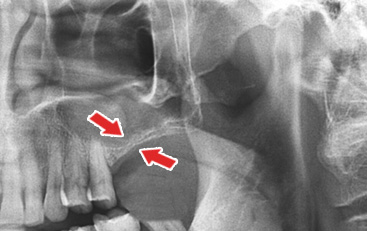

1 »ó¾Çµ¿ »ÀÀÌ½Ä Àü

³ôÀ̰¡ ³·Àº À§ÅÎ »À ¸ð½À - 2